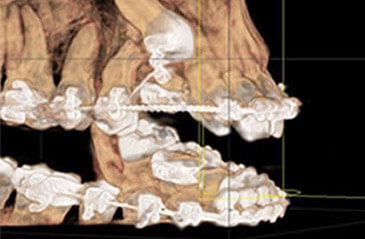

Digitales Röntgen DVT

Für den Patienten besteht der Vorteil, dass er sich oftmals nur einer einzelnen digitalen OPG unterziehen muss, damit wir einen umfassenden Behandlungsplan erstellen kann.